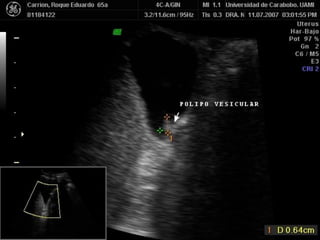

POLIPOS DE COLESTEROL

• CAUSA MAS FRECUENTE DE ENGRO-

•

SAMIENTO FOCAL

MULTIPLES: COLESTEROLOSIS

ADHERIDOS A PARED VESICULAR

NO MOVILES

NO DEJAN SOMBRA ACUSTICA